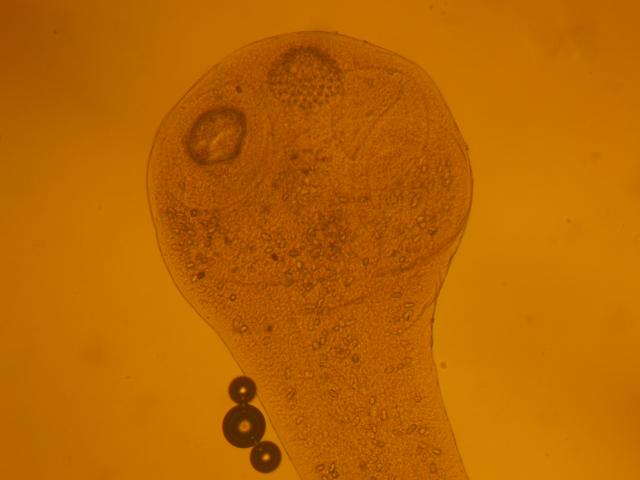

На сьогодні дерматофітози залишаються однією з важливих проблем ветеринарної і гуманної медицини, актуальність якої визначається небезпекою для здоров’я людини та значним поширенням захворювання серед собак і котів.